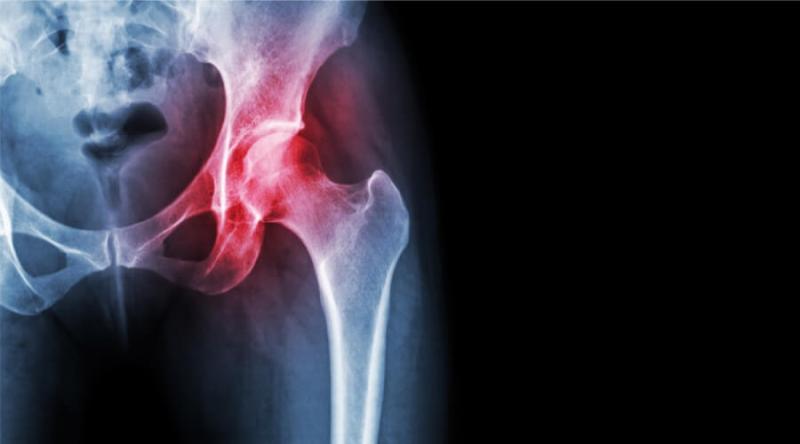

كيف تتغلب على خشونة الورك وتستعيد نشاطك؟ إذا كان يؤلمك وركك كثيرًا ، فربما تعاني من خشونة أو احتكاك في المفصل. هذ…

تعتبر أعراض التهاب مفصل الورك من الأمور المزعجة والمؤلمة التي يعاني منها العديد من الأشخاص. قد يتسب…

ألم مفصل الورك، وهو شعور غير مريح أو مؤلم في منطقة الورك أو الفخذ، وقد ينتشر إلى الركبة أو الساق. هذا الألم قد يؤ…